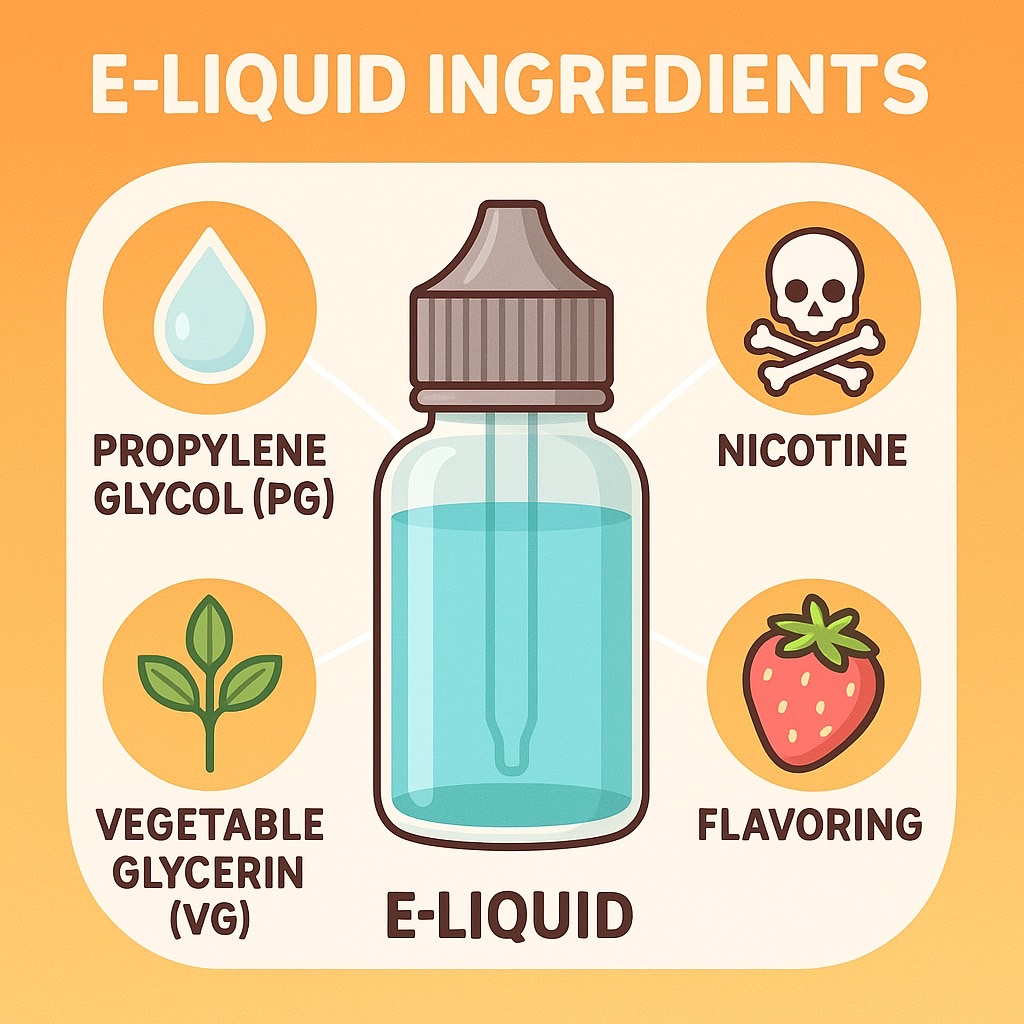

น้ำยาบุหรี่ไฟฟ้าประกอบด้วยอะไร?

น้ำยาของบุหรี่ไฟฟ้า หรือ E-liquid มักประกอบด้วย:

- นิโคติน – สารเสพติดที่ทำให้เกิดการติด

- โพรไพลีนไกลคอล (Propylene Glycol) – ช่วยกระจายกลิ่น

- กลีเซอรีน (Vegetable Glycerin) – ทำให้เกิดไอระเหย

- สารแต่งกลิ่น/รส – เช่น กลิ่นผลไม้ ขนม หรือเครื่องดื่ม

น้ำยาเหล่านี้ เมื่อถูกทำให้ร้อน จะกลายเป็นไอระเหยให้ผู้ใช้สูดดมเข้าไป